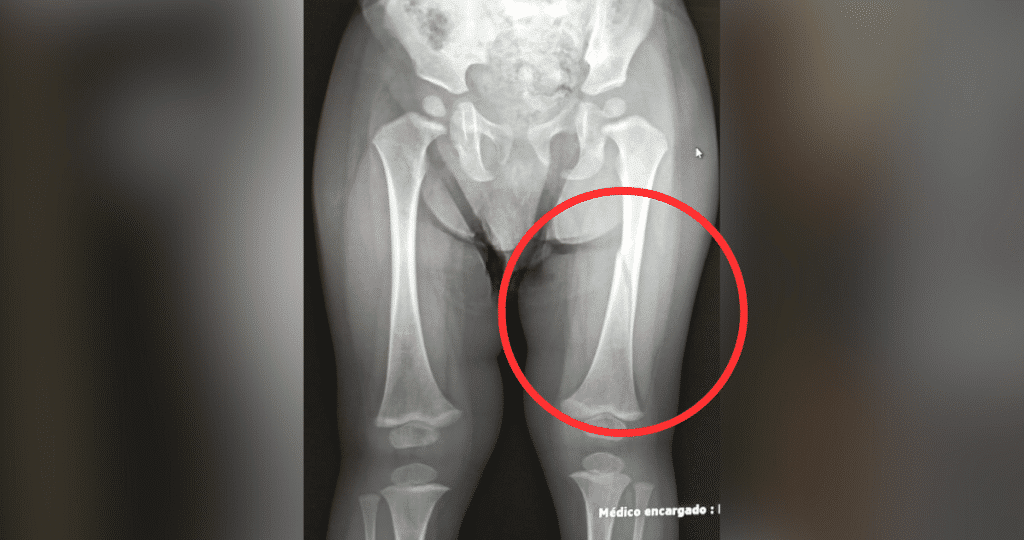

Ante la falta de acción del personal, los propios padres llevaron a Lucas a un SAR de Chiguayante. El diagnóstico fue devastador: fractura de fémur en su pierna izquierda. El pequeño fue derivado al Hospital Regional de Concepción, donde debió ser enyesado desde la cadera hasta el pie y permaneció hospitalizado por tres días.